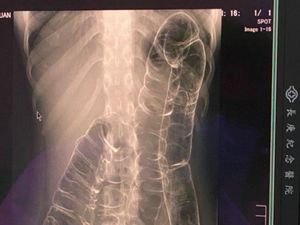

Penampakan Isi Perut Wanita yang Tak Sengaja Telan Sendok Kayu Es Krim

Seorang wanita berusia 21 tahun datang ke UGD rumah sakit. Ia mengaku tidak sengaja menelan sendok kayu saat makan es krim, begini penampakannya.